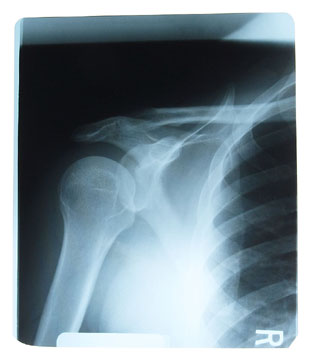

Frozen shoulder or adhesive capsulitis.

Is a condition which affects shoulder joint mobility with stiffness and pain and occurs usually between the ages of 40 and 60. Unaided recovery can be slow and symptoms can last for two to three years.

ShldrxrayW

Diagnosis

The chiropractor will be able to make an accurate diagnosis using orthopaedic and neurological tests and may suggest referral for diagnostic x-rays.